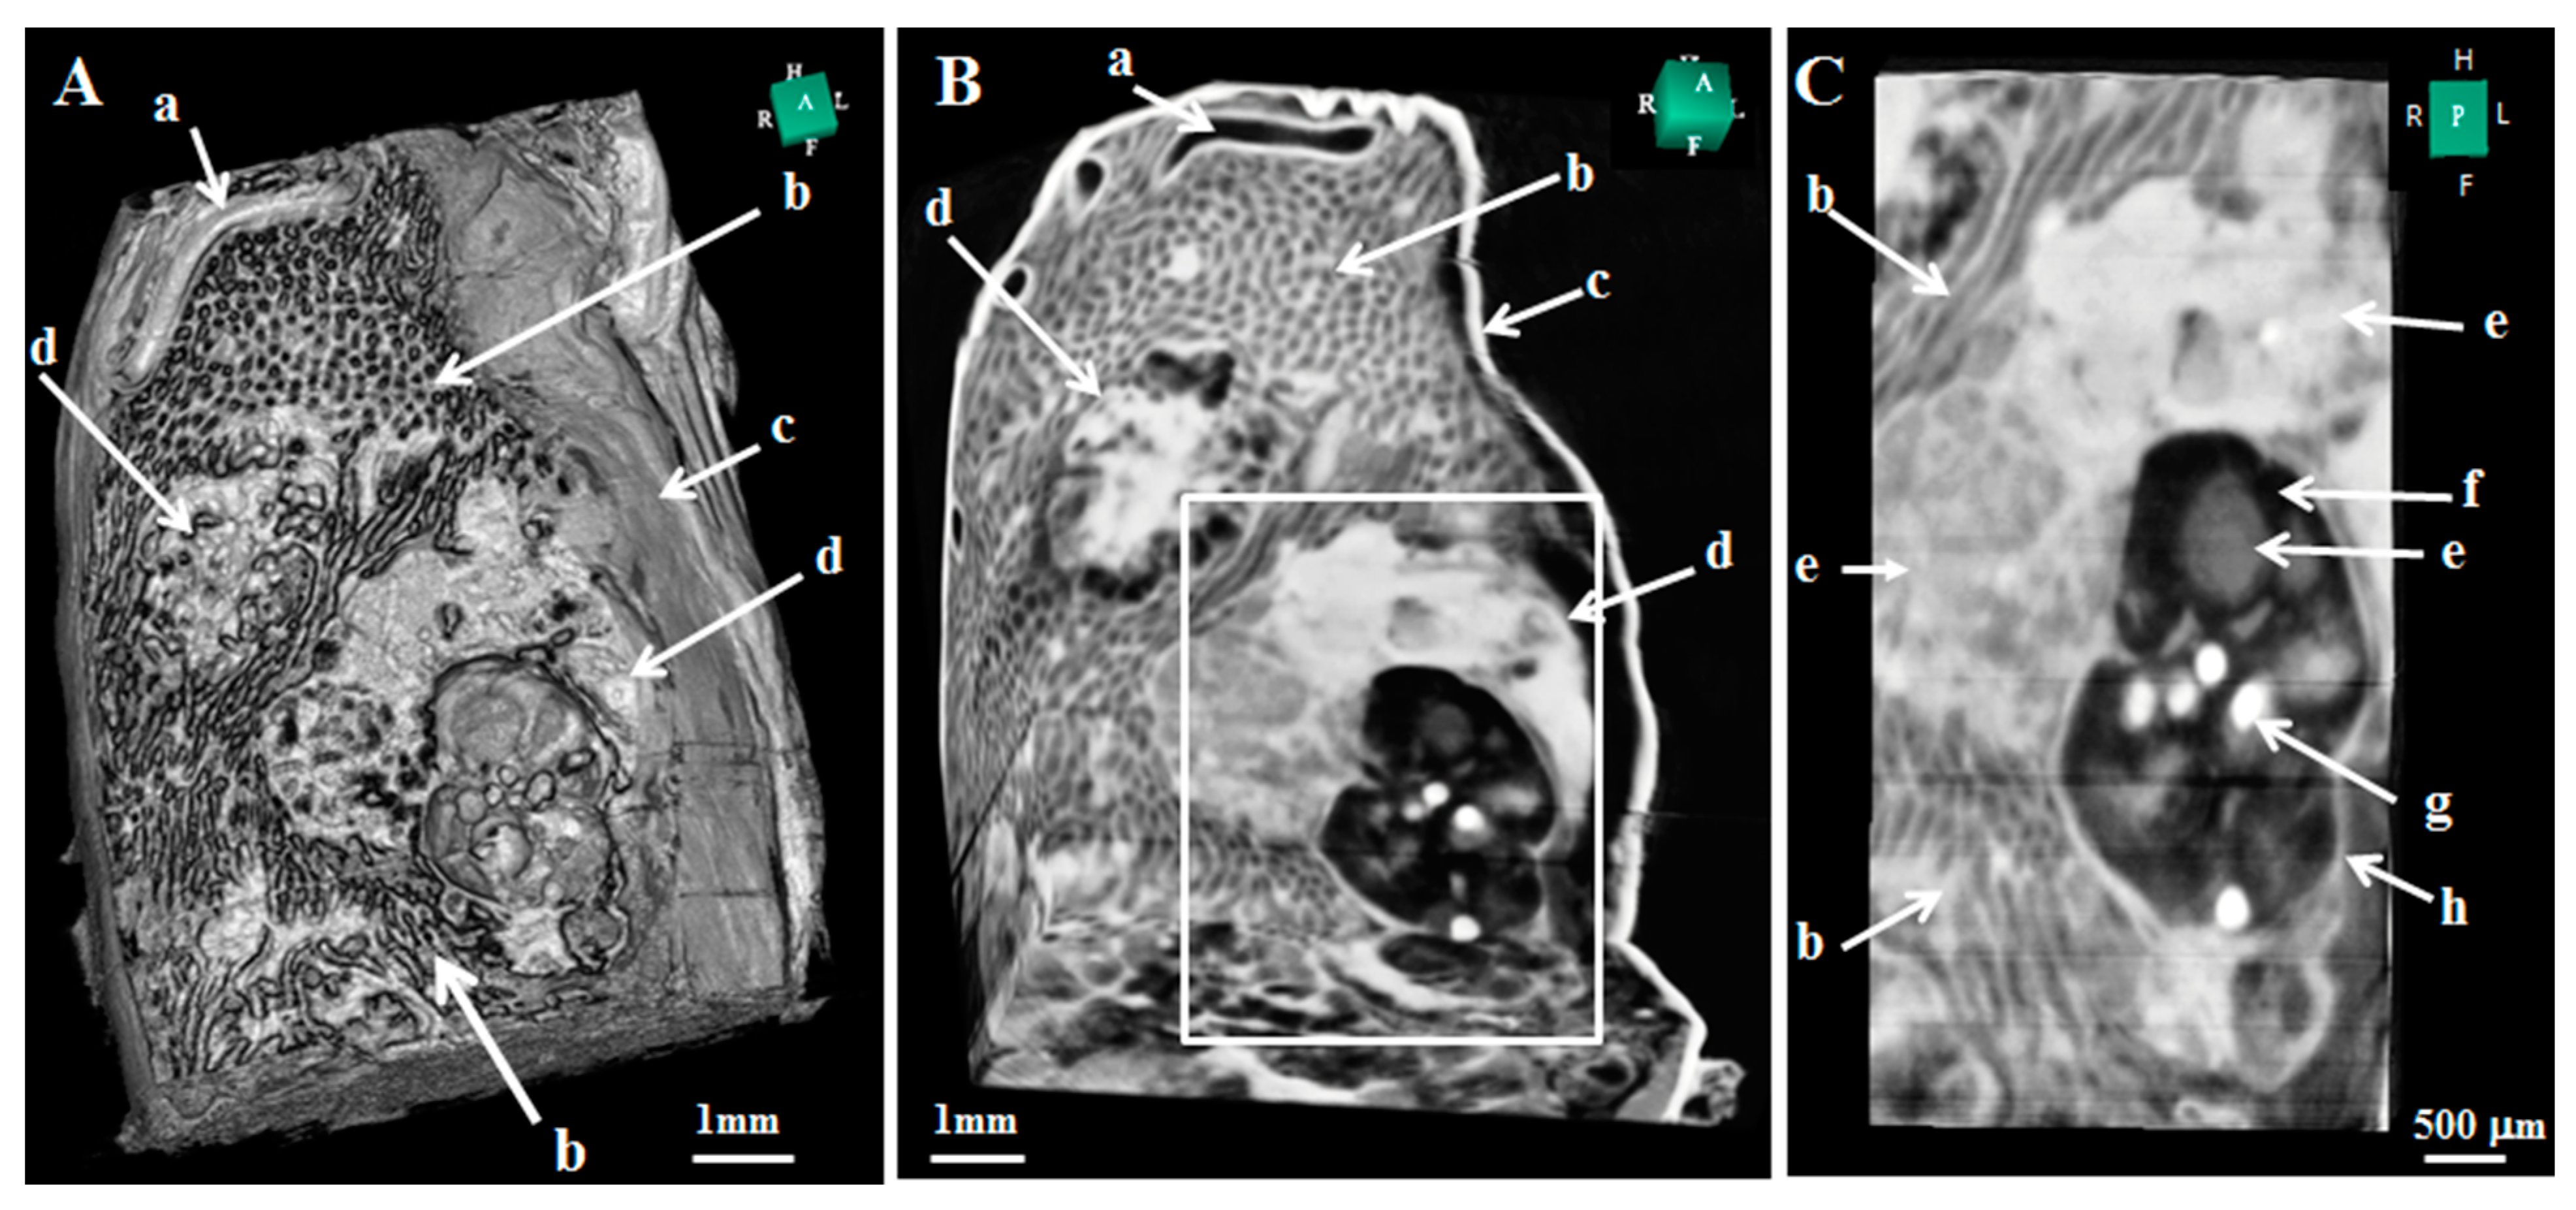

- Wu, J.; Takeda, T.; Lwin, T.T.; Momose, A.; Sunaguchi, N.; Fukami, T.; Yuasa, T.; Akatsuka, T. Imaging renal structures by X-ray phase-contrast microtomography. Kidney Int. 2009, 75, 945–951. [Google Scholar] [CrossRef] [Green Version]

- Fujii, S.; Muranaka, T.; Matsubayashi, J.; Yamada, S.; Yoneyama, A.; Takakuwa, T. Bronchial tree of the human embryo: Categorization of the branching mode as monopodial and dipodial. PLoS ONE 2021, 16, e0245558. [Google Scholar] [CrossRef] [PubMed]

- Okuno, K.; Ishizu, K.; Matsubayashi, J.; Fujii, S.; Sakamoto, R.; Ishikawa, A.; Yamada, S.; Yoneyama, A.; Takakuwa, T. Rib Cage Morphogenesis in the Human Embryo: A Detailed Three-Dimensional Analysis. Anat. Rec. 2019, 302, 2211–2223. [Google Scholar] [CrossRef] [PubMed]